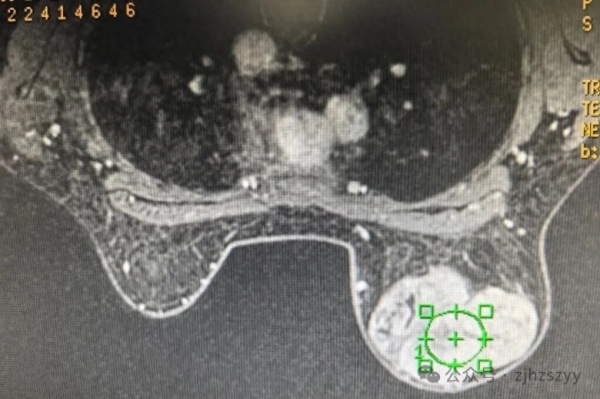

"就是自己摸到的,一开始没在意,后来慢慢变大了……"入院后检查发现,小刘的右乳肿块已达10cm×12cm,几乎占据整个乳房,外观上右乳已明显大于左侧。医生结合检查情况,建议她尽快手术切除并进行病理检查。